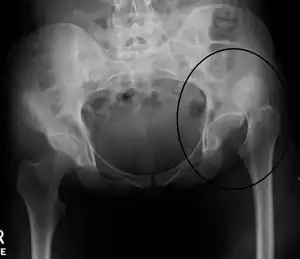

X-ray showing a joint dislocation of the left hip.

Anterior-posterior (AP) X-rays of the pelvis, AP and lateral views of the femur (knee included) are ordered for diagnosis.[13] The size of the head of the femur is then compared across both sides of the pelvis. The affected femoral head will appear larger if the dislocation is anterior, and smaller if posterior.[14] A CT scan may also be ordered to clarify the fracture pattern.

Dislocation of the left hip, secondary to developmental hip dysplasia. Closed arrow marks the acetabulum, open arrow the femoral head.